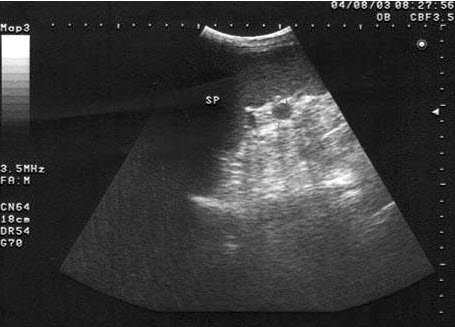

10、单项选择题

男、30岁,体检时发现脾门处光团,根据超声声像图诊断为()

A.副脾

B.淋巴结

C.转移癌

D.脾脓肿

E.左肾上腺肿瘤